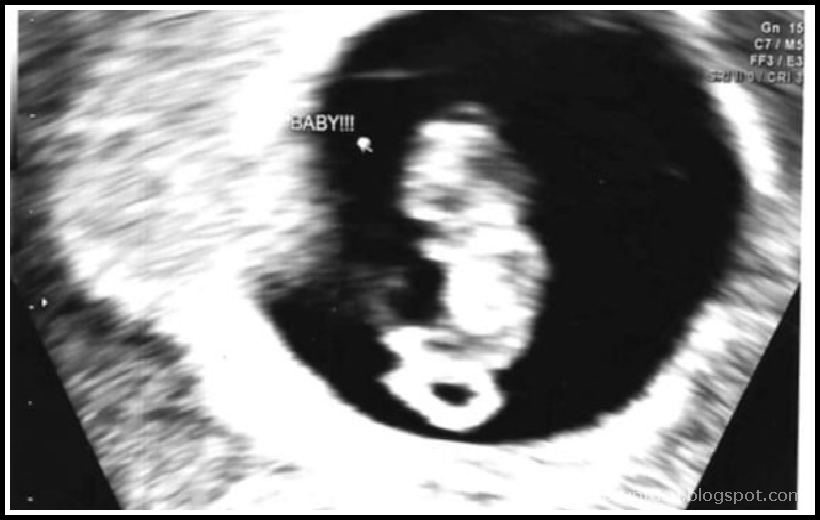

Gül’ün Gebelik Günlüğü, 12. hafta Blogcu Anne

Gül’ün Gebelik Günlüğü, 12. hafta Blogcu Anne From Pinterest